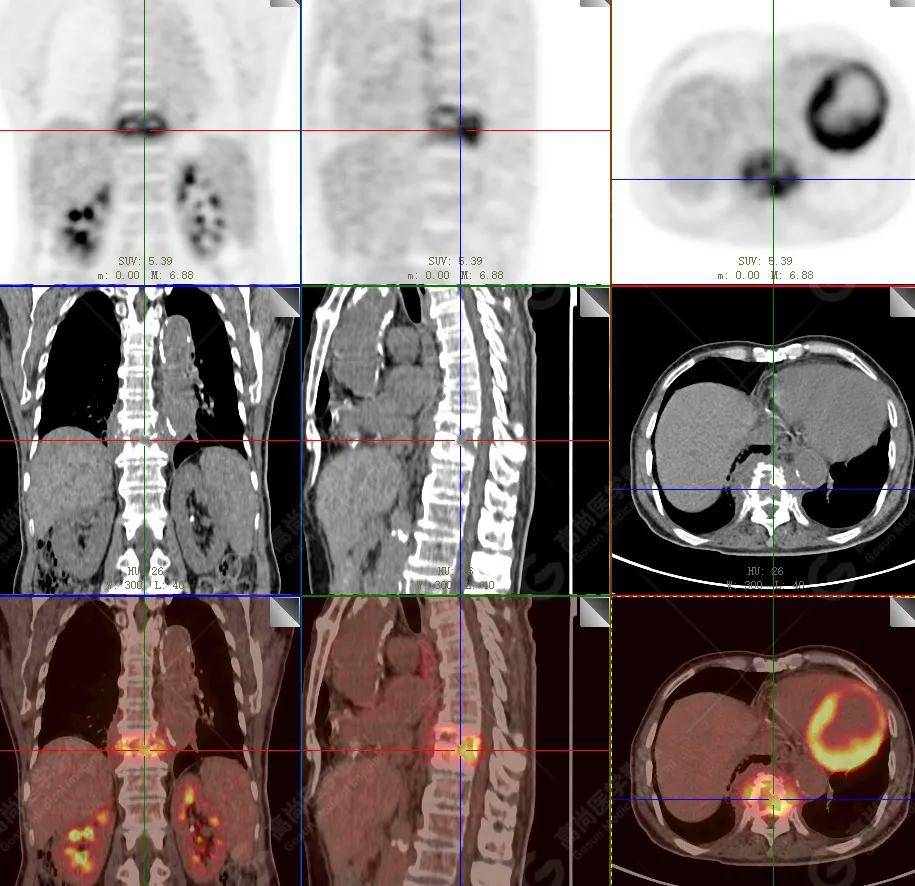

【高尚病例】18f-fdg pet/ct显像应用于骨结核